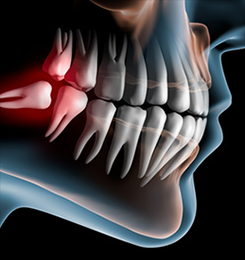

歯の状況によっては抜歯等の外科的処置も行っています。また、口を開けると顎がカクカク鳴る、顎が痛い、口が開けにくい等の症状で不安に思われている方もご相談ください。